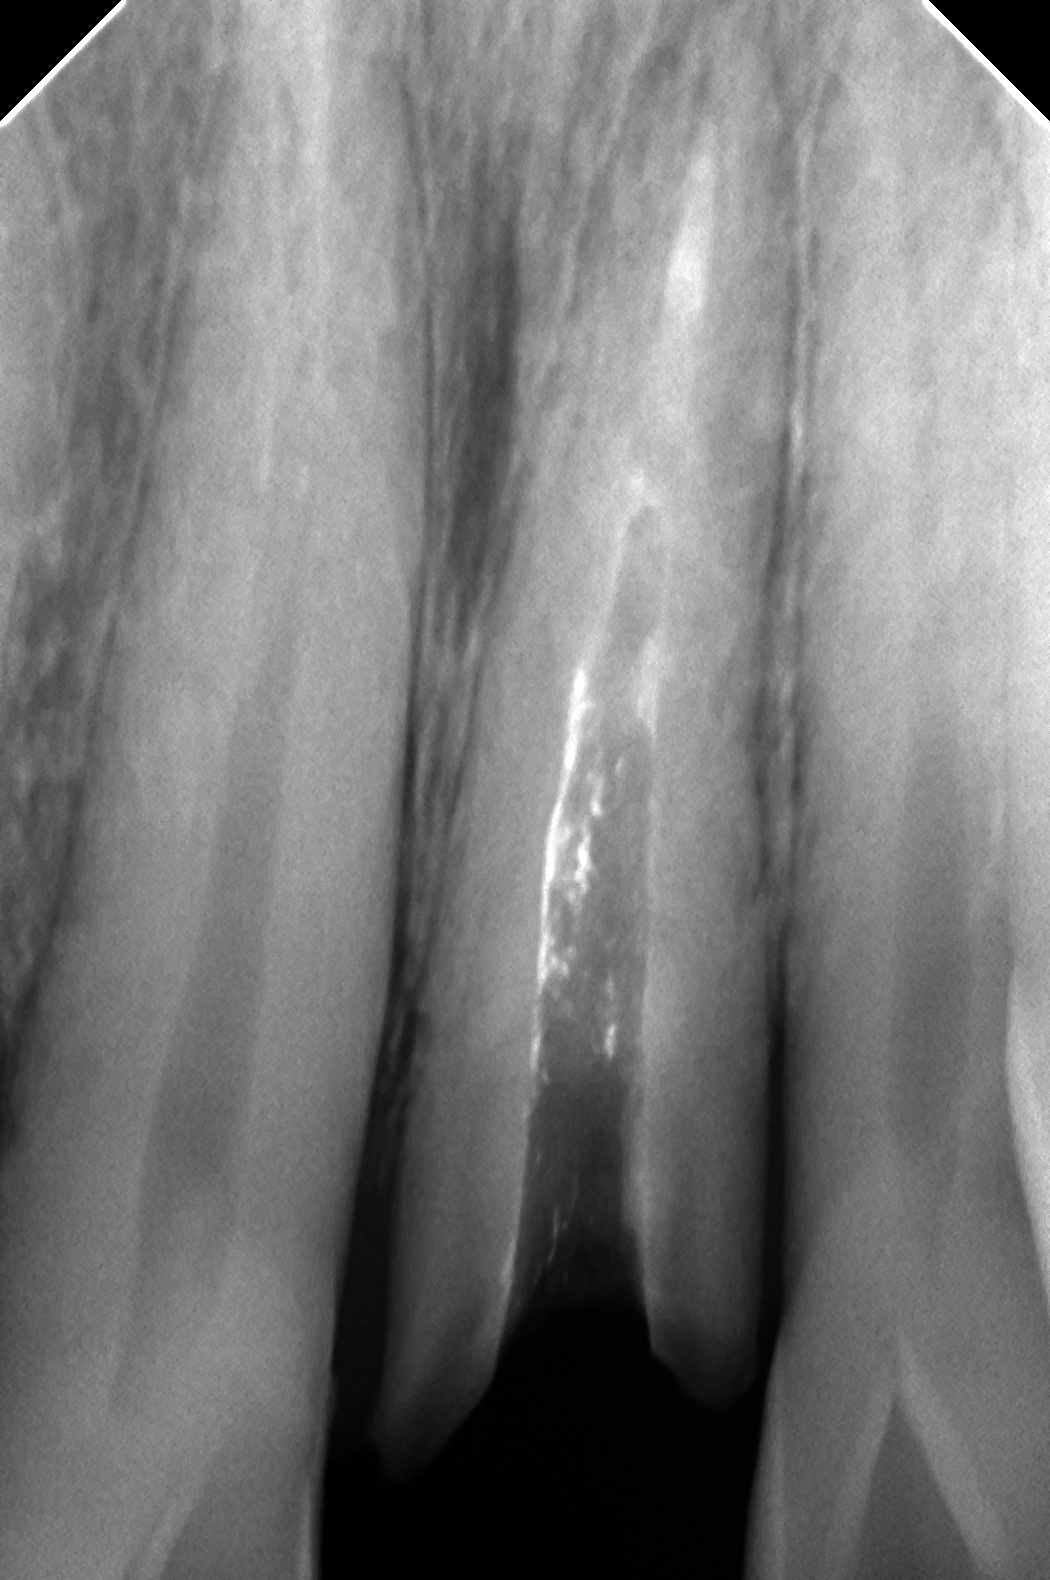

鋳造欠陥はなはだしい笑メタルコアが割れています。

普通に削り飛ばすと、時間かかるし、歯も削っちゃいそう・・・

んで、マイクロあれば5分くらいで

上のほうを削り、金属の薄いところを作り、マイクロで超音波を使いながらぺりぺりはがすと、歯も傷つかないしかんたんですね(^^♪

これ、マイクロないとすごく時間かかります・・・